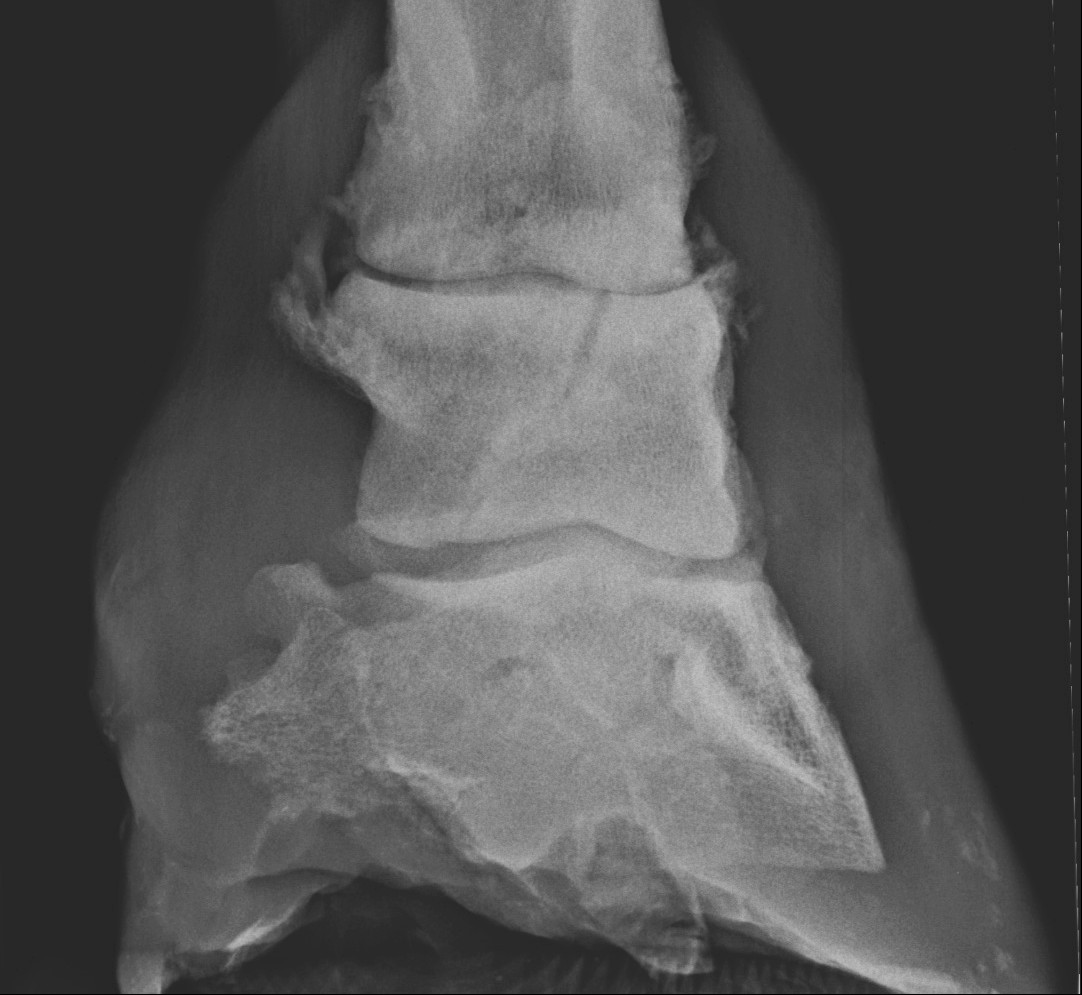

A ficamok szerencsére nagyon ritkák. Szinte biztosan műtéti, de legalább kórházi ellátást követelnek. A törések kicsit gyakoribbak. Még mindig sokan úgy hiszik, hogy csonttörésből nem épülhet fel ló, pedig többször meggyógyulnak, mint ahányszor nem! A legtöbb törés műtéti ellátást igényel. A törések diagnosztizálása néha nagyon nehéz, CT felvétel készítésére is szükség lehet!

A törések elbírálásánál a következő tényezőket kell megvizsgálni:

- A ló kora: fiatal lónak jobbak a gyógyulási paraméterei, így több az esélye.

- A törés helye: mennél lejjebb van a törés, annál jobbak az esélyek.

- A törés jellege: az egyszerűbb törések sokkal könnyebben gyógyulnak és műthetőek, mint az összetett, romtörések.

- Ha a törés ízületbe terjed, rosszabb az esély, hiszen az ízület is károsodhat emiatt.

- Ha a törés nyílt, drasztikusan csökkennek a gyógyulás kilátásai.

A pártacsont törése súlyos ízületi degenerációhoz vezetett